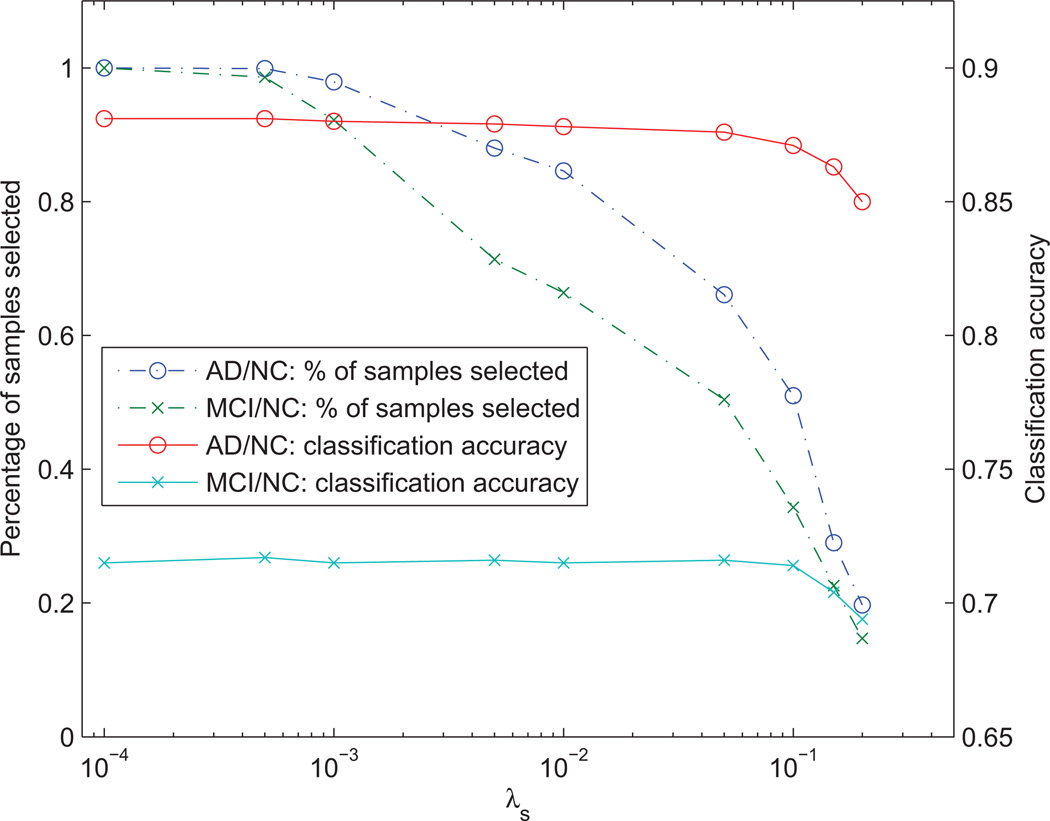

4.5. Effect of λs on sample selection

Figure 5 shows the effect of λs on sample selection in Eq. (2) to the average number of samples selected (from the training dataset) and the average classification accuracy (i.e., accuracy of the label imputation) of the matrix completion. As shown in Figure 5, the average number of samples selected reduces gradually when λs is decreasing, while relatively consistent in terms of classification accuracy for mFPC. This implies that there are a lot of redundant samples in the training set, which can be removed without significantly affecting the accuracy of the label imputation. To examine the performance of sample selection using synthetic data, please refer to Appendix A.

Figure 5.

Effect of the parameter λs on the number of samples selected and the corresponding classification accuracies for AD/NC and MCI/NC classification using mFPC of the proposed framework.

One of the possible limitations of the proposed sample selection is that the output space is not considered in the algorithm (as this information is not available for the testing samples), which might cause possible bias in the result if there is measurement noise in the output space. For example, the feature space for highly coherent samples is very similar, but due to measurement noise in the output space, they may have different outputs. In worst case scenario (e.g., using too large λs value), the l1-regularized algorithms (i.e., the l1-norm part of the l2,1-norm) may select only one sample and discard the others, which cause bias in the result. This problem can be ameliorated by including the additional l2-regularization, such as that done in Elastic Net (Zou and Hastie, 2005). This will help retain some coherent samples and allow some averaging effect. Another possible solution is to perform sample selection and output variable estimation iteratively, which we leave it as our future work.